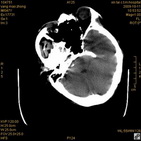

病人杨XX,男,青云街道办事处路踏泉村,住院号51666,CT号:104770。病人因“高血压脑出血”在新泰市人民医院住院治疗5天,治疗效果不佳转入我院,复查CT示左基底节血肿,病人昏迷状态,给予血肿清除术,术后2天复查CT,血肿完全清除,病人恢复好,治疗效果满意。附病人术前术后CT片资料如下。

术后46小时复查CT

术后46小时复查1 术后46小时复查2 术后46小时复查3 术后46小时复查4